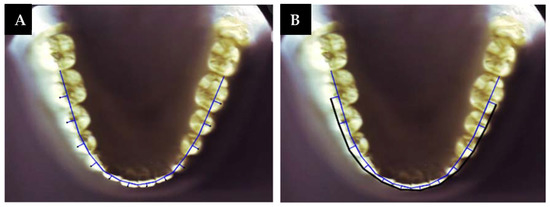

To establish the clinical bracket points for every anterior tooth and premolar, a perpendicular line was drawn to extend facially from the midpoint of the line that connects the mesial and distal contact points [4,6,9,12]. This was based on Andrew’s data on the prominence of the crown [26]. In the molars, this line was drawn from the region where the mesial third meets the distal two-thirds. Another line connecting the clinical bracket points was drawn to determine the arch form (Figure 2). Afterwards, the digital model was printed on a 1:1 scale. Then, the three different arch forms (tapered, ovoid, and square) were identified using the 3M Unitek templates. This was carried out relying on an arch form that provides a proper fit for the eight clinical bracket points from the right to the left first premolars [27] (Figure 3).

Figure 2. (A) Clinical bracket points; (B) contact point and clinical bracket point lines.